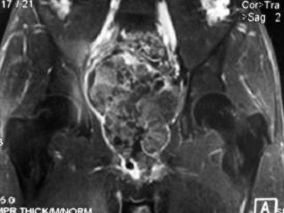

关于前列腺肉瘤 你想知道的都在这个病例中

1小时条评论【病例资料】 患者男性,19岁。 主诉:进行性排尿困难伴间断性全程肉眼血尿1个月余,排便困难2周。 现病史:患者1个月前无明显诱因出现排尿费力,尿线变细,伴尿痛,为耻骨后疼痛,自行口服抗生素,疗效不佳;25天前突然出现间断性全程肉眼血尿,伴尿痛,无尿急、...